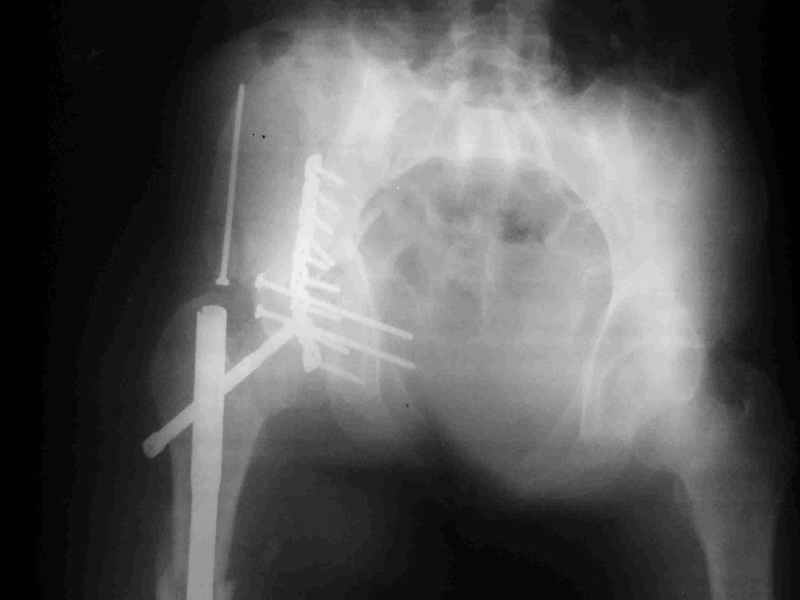

К сожалению, набора для ретроградного или антеградного реконструктивного штифтования в операционной нет, поэтому доставка заняла н-ное время. Вопрос, который возник у меня- по поводу оптимальной тактики хирургии: вся фиксация в один этап из расширенного доступа или последовательно сначала бедро и позже реконструкция впадины, комбинированный доступ к впадине отдельно к передней и задней колоннам или из расширенного илеофеморального одного доступа. Все-таки решил остановиться на одноэтапном подходе и спустя 5 дней (как раз и наборы привезли) из расширенного илеофеморального доступа сначала фиксировал реконструктивным штифтом Smith&Nephews бедро и

шейку (благо перелом шейки 2 типа -относительно стабильный) затем фрагмент крыла подвздошной кости Lag screw, далее пластина на заднюю колонну и винты в переднюю колонну.(с размерами и направлением винтов ошибка вышла:-((, но интраоперационно у меня была полная уверенность , что винты *ушли* в лонную кость).

Еще раз спасибо за комментарии и готовность помочь с имплантами. Постоп картинки в приложении,

-С идеей extended iliofemoral approach согласен, хотя он очень травматичный, если Вы выбрали данный доступ, то пластина должна сидеть снаружи на супра ацтабулярной поверхности?

Доступ травматичный, обширная диссекция ягодичных мышц, бедренных ротаторов, но для меня на данном этапе необходимо получить ясное представление о методологии репозиции,( хоть русский язык и богат, но английский более компактно передает идею:-)), словом - hand in experience и как только это